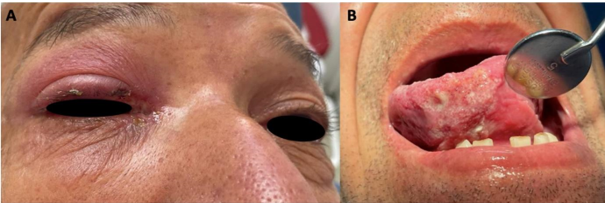

Paciente masculino en sexta década de vida, de profesión agricultor, sin antecedentes de importancia, quien acude a consulta de Cirugía Maxilofacial del Hospital San Vicente Fundación con cuadro de dolor en la lengua y ojo derecho (OD), acude con resultados de histopatología por toma de biopsia a nivel de OD con resultados de queratoacantoma. Clínicamente presenta equimosis palpebral superior, costras serosas en canto interno que se extiende por región de placa tarsal superior, equimosis conjuntival de 360 grados, pupilas isocóricas y normorreactivas a la luz, esclera de ojo izquierdo (OS) anictérica, movimientos oculares conservados, capa de tejido fibroso, de color blanquecino transparente que se extiende desde canto interno de OS hasta córnea ipsilateral que se relaciona con pterigión (Fig. 1a).

Al examen estomatognático se observa en la cara ventral de lengua del lado derecho lesión de tipo granulomatoso, de aproximadamente 6 cm de diámetro extendiéndose hasta los bordes laterales de lengua ipsilateral, compuesta por zonas blanquecinas tipo pseudoplaca las cuales desprenden al raspado, adyacente a éstas lesiones eritematosas puntiformes de aproximadamente 1 mm de diámetro, de tiempo de evolución de aproximadamente 1 año, asintomática a la palpación, de bordes irregulares no indurados y bien definidos, en el momento de etiología desconocida (Fig. 1b).